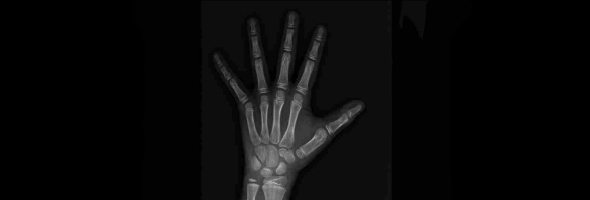

在骨骼健康管理中,“骨龄”与“骨密度”常被并列提及,但二者本质截然不同:前者是生物年龄的“时间刻度”,后者是骨骼质量的“密度标尺”。本文将从医学原理、检测技术、临床意义三个维度,揭开这对“双生密码”的神秘面纱。

骨龄与骨密度有什么区别?解析两者的定义、检测与应用

中华05标准骨龄检测:精准评估儿童发育,解码成长密码

在儿童健康管理领域,骨龄检测如同“成长密码”,精准解码孩子的生物学年龄与发育潜力。它不仅反映生物学年龄,更预示着身高潜力乃至代谢健康。本期我们就来探讨一下中华05骨龄评测标准,看看它为何在儿童生长发育领域备受关注。